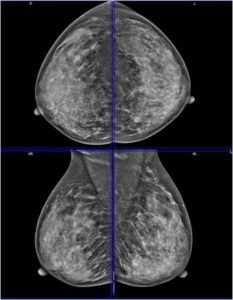

48 year old female came for routine mammographic screening...

Read More